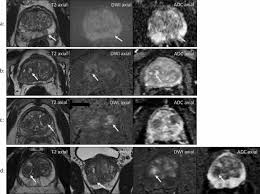

Cancers Free Full Text Correlation Between Intraprostatic Psma Uptake And Mri Pi Rads Of 68ga Ga Psma 11 Pet Mri In Patients With Prostate Cancer Comparison Of Pi Rads Version 2 0 And Pi Rads Version 2 1 Html

Cancers Free Full Text Correlation Between Intraprostatic Psma Uptake And Mri Pi Rads Of 68ga Ga Psma 11 Pet Mri In Patients With Prostate Cancer Comparison Of Pi Rads Version 2 0 And Pi Rads Version 2 1 Html from www.mdpi.com